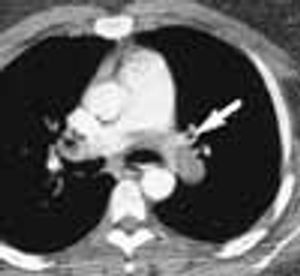

For 2 months, a 31-year-old woman had had dyspnea and dull, continuous retrosternal pain. She was admitted to the hospital, and a helical CT scan of the thorax identified a saddle pulmonary embolism. An ultrasonogram revealed deep venous thrombosis (DVT) in the left leg. Intravenous heparin was given; the patient was discharged, and warfarin was prescribed.